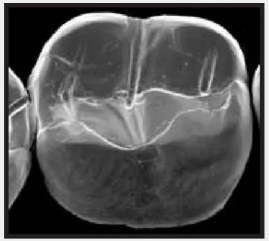

復合樹脂在即刻充填后,觀察其在電子顯微鏡下的掃描圖像,本次研究選擇了9種具有代表性的復合樹脂材料。

2.png

IPS Empress Direct Ivoclar Vivadent義獲嘉維瓦登特